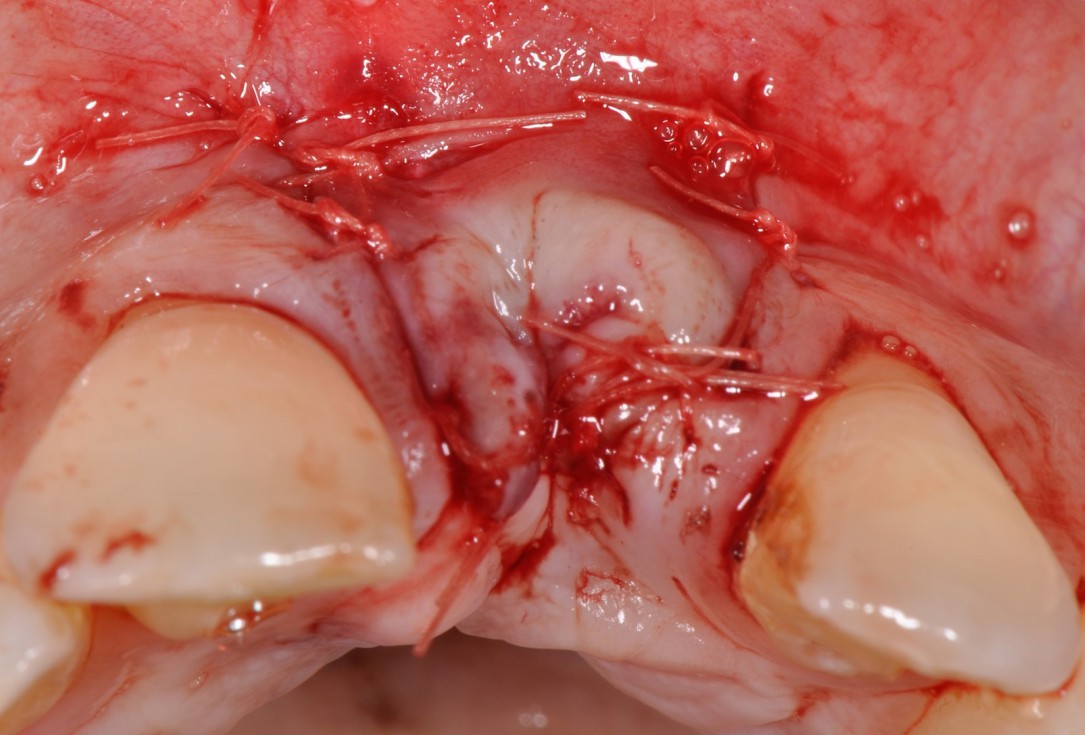

Immediate implant placement with cerabone® and mucoderm® - Dr. F. Rossi - Tension-free wound closureImmediate implant placement with cerabone® and mucoderm® - Dr. F. Rossi